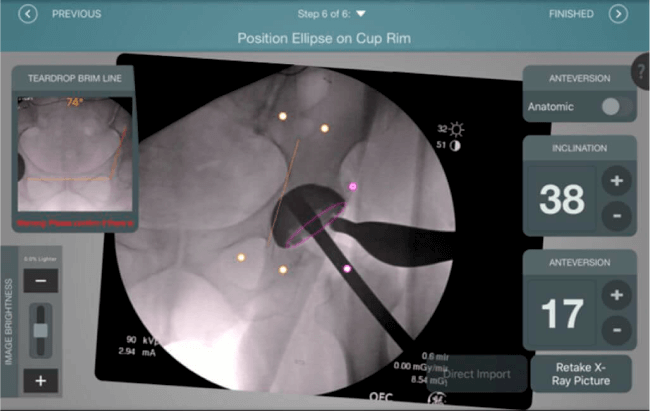

Inclinación y anteversión de la copa acetabular para una correcta colocación del implante.